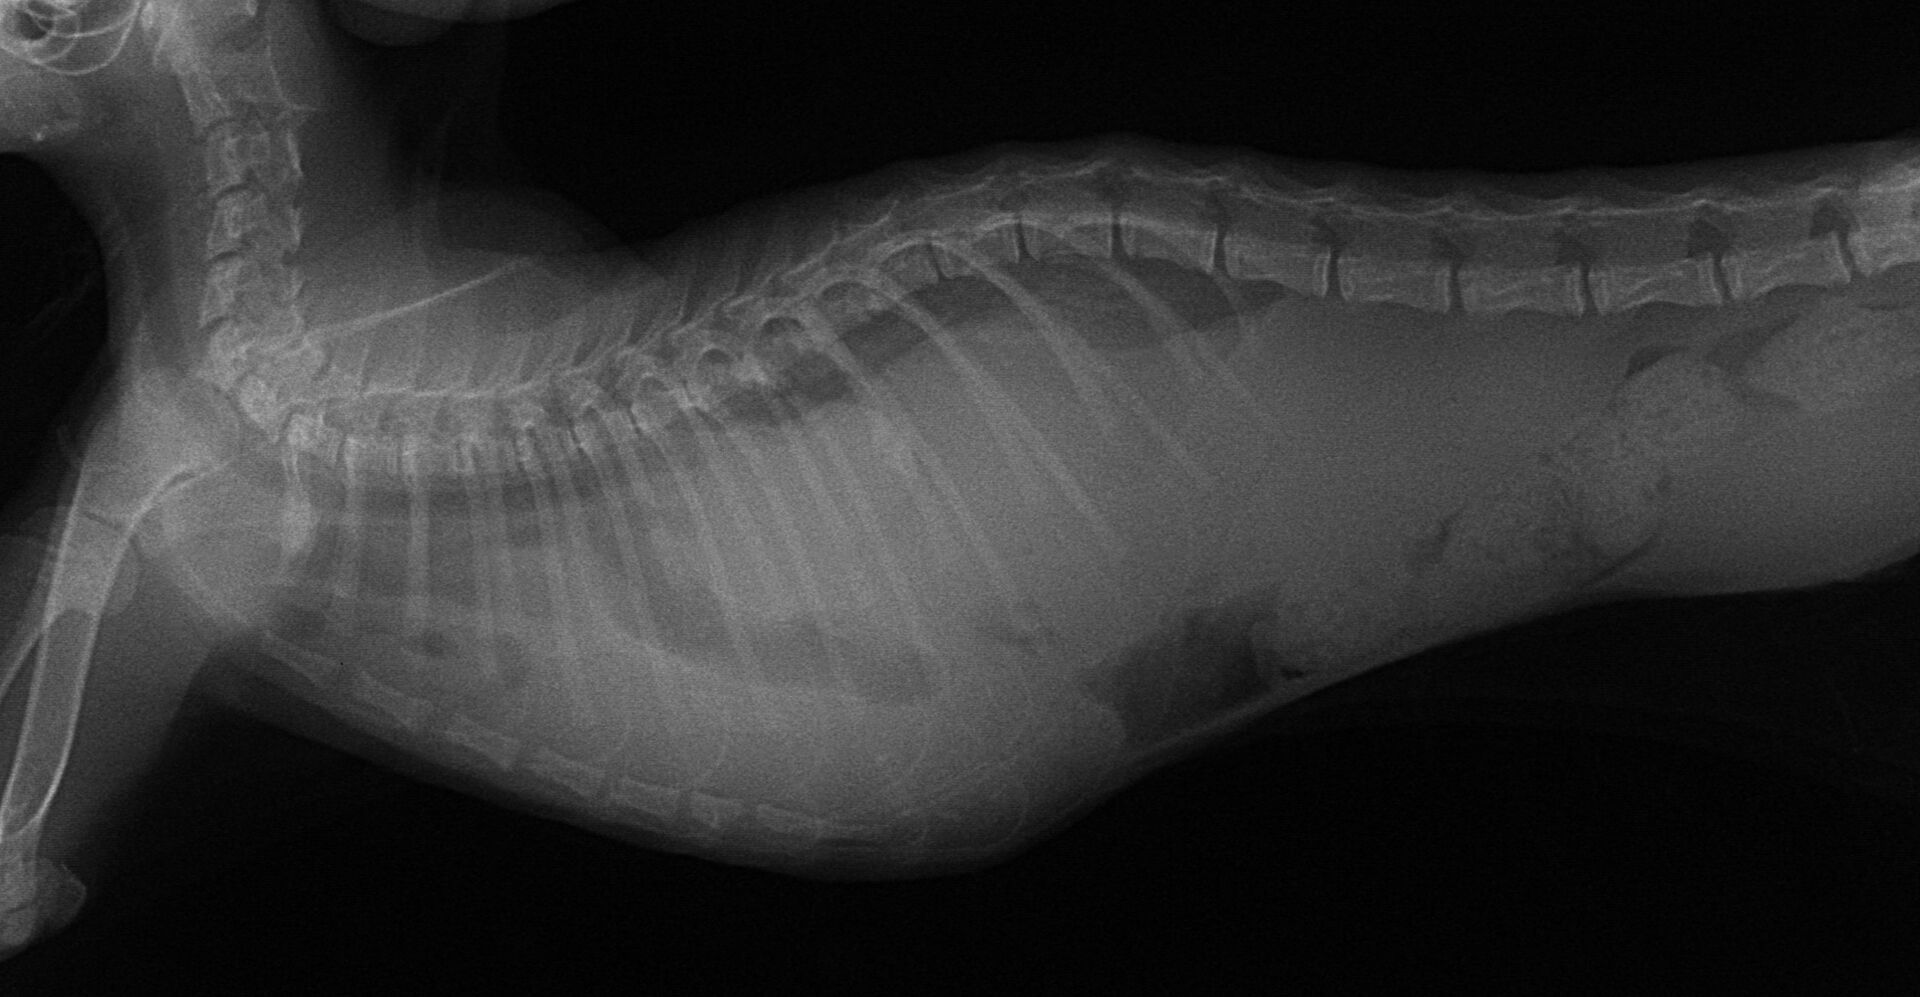

お久しぶりです。久々の症例報告です。12月中旬の日曜日に新規の飼い主さんから電話をいただきました。当院の近くの動物病院で診てもらっていたが手術ができないと言われたという。子猫が横隔膜ヘルニアになって死にそうになっているので、何とか手術ができないか、ということでした。すぐに連れてきていただきました。診れば体重は1㎏未満で、呼吸が浅くて体温もかなり低く、危険な状態でした。すぐにレントゲンを撮りました。それが以下の写真です。

胸部にあるはずの肺は、腹部の臓器である肝臓や胃、腸に押しつぶされている状態でした。こうなると肺を膨らませることができず、常に酸欠状態になります。すぐにICUに入れ呼吸を助けてあげました。少し落ち着いた状態になりました。血液検査で状態を把握し、それに応じて点滴をし、その夜に手術する予定にしました。